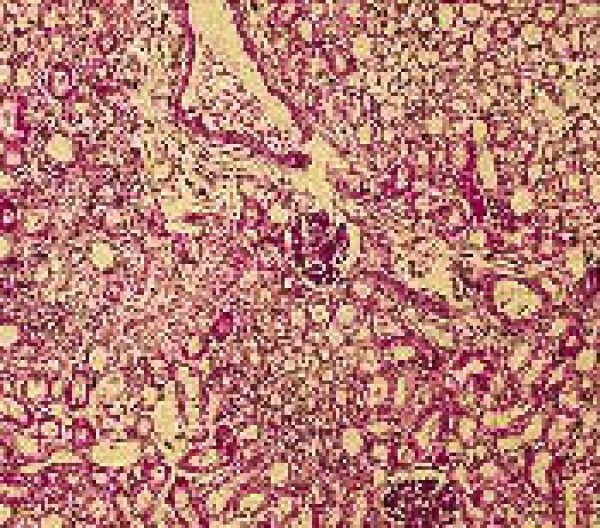

Patología neonatal. Aspecto histológico característico del riñón de un cachorro infectado por el herpesvirus canino (inclusiones herpéticas).